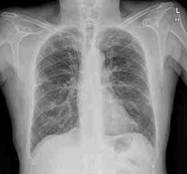

La

Enfermedad Pulmonar

Obstructiva Crónica (EPOC) es un desorden respiratorio crónico que comprende

a la bronquitis crónica y al enfisema pulmonar, y está caracterizado por

exacerbaciones definidas como: